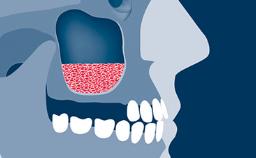

- explain the rationale for contour augmentation using guided bone regeneration (GBR)

- list the materials used for contour augmentation in esthetic sites

- describe the surgical steps and considerations that precede simultaneous augmentation

- describe the treatment concept and surgical steps for simultaneous contour augmentation